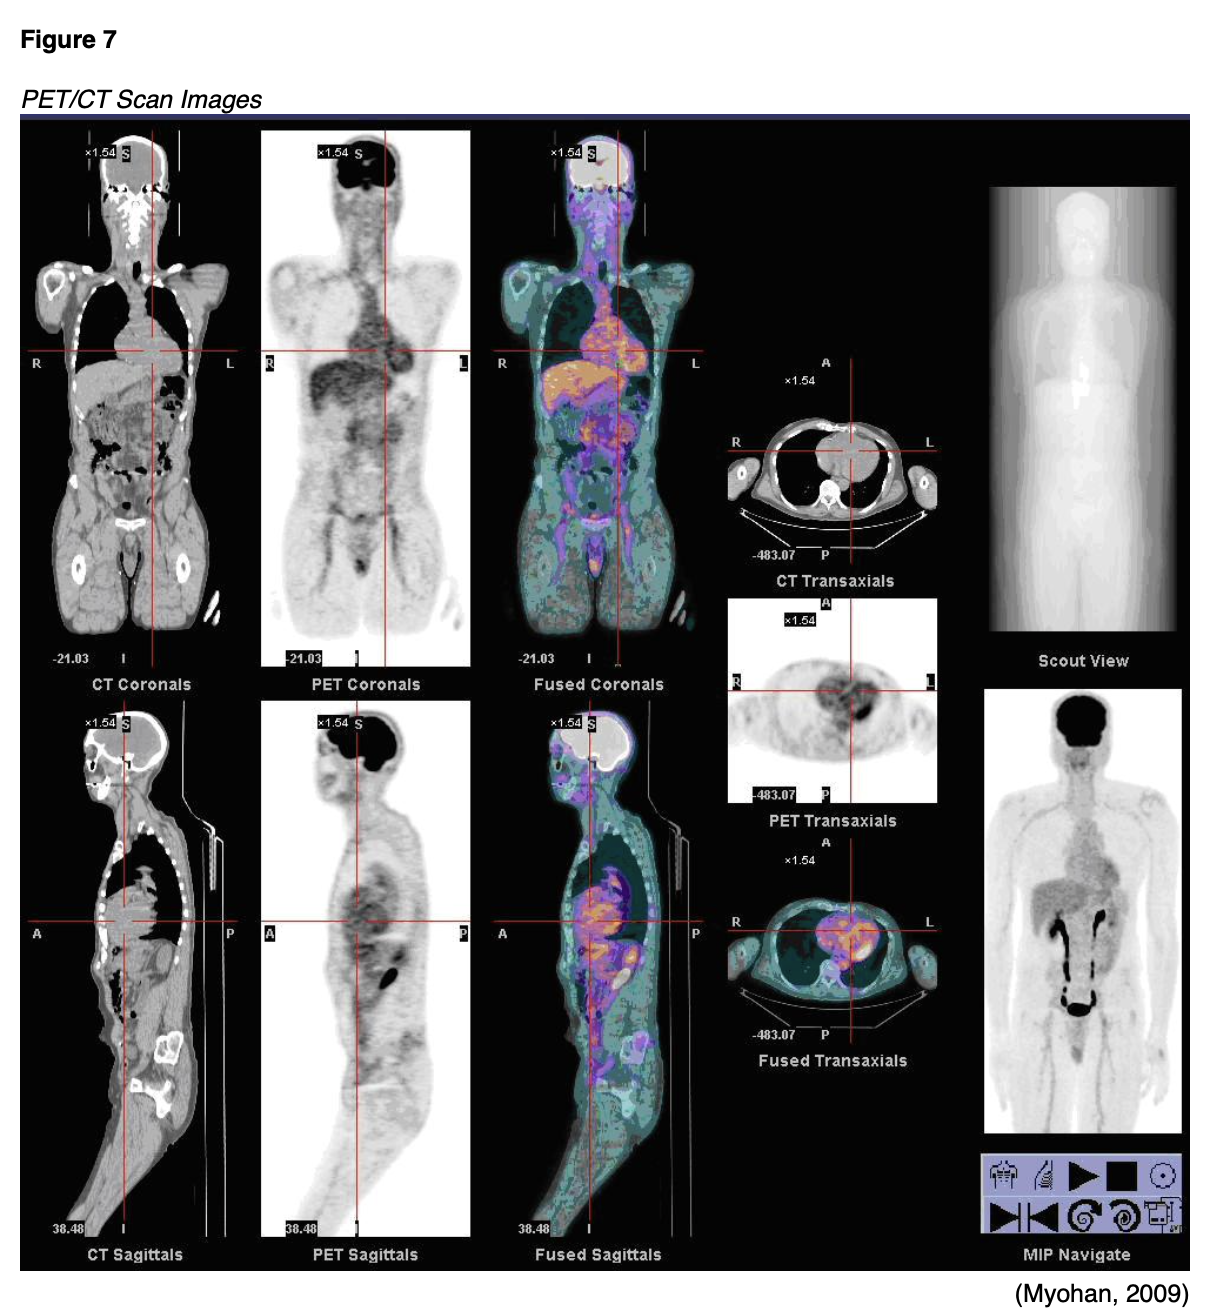

PET/CT imaging uses the radiotracer fluorodeoxyglucose (FDG) to create 3D images and is combined with CT scans to better locate areas of abnormal cell activity. There are a few types of PET/CT scans, but the most common is a full-body PET/CT, which evaluates the internal structures from the mid-portion of the skull down to the thigh area ("eyes to thighs"), in combination with a low dose CT scan. This is a hybrid imaging modality; the resulting images acquired from each test are fused using advanced computerized technology to create enhanced images of higher quality. The functional imaging obtained by the PET scan illustrates the spatial distribution of metabolic or biochemical activity in the body, which is then more precisely aligned with the anatomic imaging obtained by the CT scan. PET/CT scans provide superior information for evaluating tissues, the staging and restaging of cancers, and are useful for monitoring the effectiveness of cancer treatments. Since cancer cells take in glucose faster than normal tissue, the FDG tracer is a superior radiotracer for evaluating cancerous tissue, as FDG is a compound similar in chemical composition to glucose. The FDG accumulates in areas of the body that are most metabolically active, which helps differentiate between physiologic uptake (healthy tissue) and pathologic uptake (diseased tissue; Thayalan, 2014).

The FDG radiotracer is injected into the patient's bloodstream, and the PET/CT scan creates images that show the distribution of the radiotracer throughout the body and determine if abnormalities are present. Highly active cancer cells show higher levels of uptake of FDG, whereas brain cells affected by dementia consume smaller amounts of glucose, indicated by lower FDG uptake (Memorial Sloan Kettering Cancer Center [MSKCC], 2019). An example of the resultant images obtained from a PET/CT scan are displayed in Figure 7.